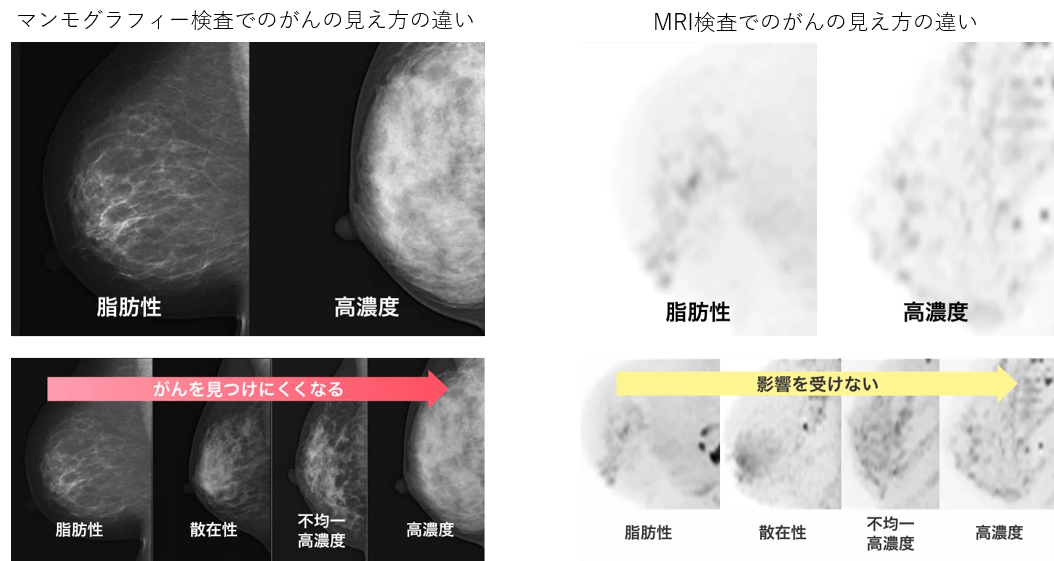

日本人は欧米と比べて高濃度乳腺の割合が高く、50歳以下では80%近くが高濃度乳房(高濃度・不均一高濃度)であるとする報告があります。

無痛MRI乳がん検診は、乳腺の量に左右されにくいので、がんの発見率が下がることはありません。日本人女性に多い高濃度乳房(デンスブレスト)の方でも、安心して検査を受けることができます。

マンモグラフィの場合、がんは白く写りますので「雪山の白ウサギ」をみつけるような感じになり、当然がんがみつかりにくくなります。無痛MRI乳がん検診では、がんが黒く映ります。無痛MRI乳がん検診では、マンモグラフィでは見分けのつきにくいがんが次々に発見されています。